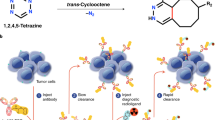

Pretargeted imaging allows the use of short-lived radionuclides when imaging the accumulation of slow clearing targeting agents such as antibodies. The biotin-(strept)avidin and the bispecific antibody-hapten interactions have been applied in clinical pretargeting studies; unfortunately, these systems led to immunogenic responses in patients. The inverse electron demand Diels-Alder (IEDDA) reaction between a radiolabelled tetrazine (Tz) and a trans-cyclooctene (TCO)-functionalized targeting vector is a promising alternative for clinical pretargeted imaging due to its fast reaction kinetics. This strategy was first applied in nuclear medicine using an 111In-labelled Tz to image TCO-functionalized antibodies in tumour-bearing mice. Since then, the IEDDA has been used extensively in pretargeted nuclear imaging and radiotherapy; however, these studies have only been performed in mice. Herein, we report the 44Sc labelling of a Tz and evaluate it in pretargeted imaging in Wistar rats.

The theranostic approach has been an important factor in the recent developments in radioimmunotherapy mainly due to pretherapeutic dosimetry and measuring treatment response [4]. One of the main drawbacks in radioimmunotherapy though is the sub-optimal pharmacokinetic properties of the antibodies. Due to their long circulation time and slow target accumulation, the radiation burden to the patient can be quite high. This necessitates the use of long-lived radioisotopes further increasing the radiation dose. This can be mitigated with a pretargeting strategy. With this method, there is a temporal separation of the targeting step from the delivery of the radiation at the target site. The process involves a primary agent and a secondary agent, each functionalized with tags that specifically bind to each other in a biological medium. This method can be applied using bioorthogonal chemical reactions such as the inverse electron demand Diels-Alder (IEDDA) reaction, namely the trans-cyclooctene (TCO)-tetrazine (Tz) ligation. The first application of this method in nuclear medicine involved a tetrazine labelled with indium-111 via the 1,4,7,10-tetraazacyclododecane-1,4,7,10-tetraacetic acid (DOTA) chelator (1) [5]. Following this success, a number of Tz have been developed for diagnostic purposes [6,7,8,9], but also a few DOTA-Tz have been labelled with therapeutic isotopes such as lutetium-177 and lead-212 with the hope of providing pretargeted radioimmunotherapy [10,11,12].

The aim of the current study was to develop a 44Sc-labelled variant of 1 and evaluate its use for pretargeted PET imaging. The primary agent was a TCO-functionalized variant of the bisphosphonate, alendronic acid (Aln-TCO, 2) (Fig. 1). Alendronic acid is used in the clinic to treat osteoporosis, and it accumulates in areas with high bone turnover [20]. TCO-modified alendronic acid has been used to screen radiolabelled tetrazines for in vivo pretargeting in healthy mice [21,22,23] [20, 24, 25]. The possibility to screen in healthy animals is advantageous for applications in higher order species because a disease model is not needed. Furthermore, TCO-modified alendronic acid accumulates at their target sites quickly and exhibits fast clearance from non-targeted tissues. Consequently, clearing agents or lengthy pretargeting lag times are not required as in the case with TCO-functionalized antibodies [21]. One of the challenges in using bioorthogonal reactions for pretargeted imaging is that the reaction kinetics are concentration dependent. This can alter the effectiveness of the reaction when moving from smaller living species to larger ones. For example, early studies applying the Staudinger ligation in vivo were successful in cells, yet the system failed once it was applied to mice models [26,27,28]. To date, pretargeted imaging using the TCO-Tz ligation has only been reported in mice (ca. 20 g). Various radiolabelled bisphosphonates have been evaluated in healthy Wistar rats as potential agents to image bone metastasis leading to clinical evaluation in patients with skeletal metastases [22, 23, 29, 30]. Therefore, the current pretargeted imaging studies were performed using the larger Wistar rats (ca. 150+ g).